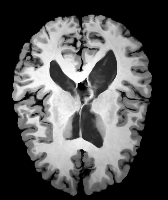

Results: All trained networks are evaluated using Dice overlap scores between predictions and the manual segmentations for the segmentation network, or between the warped moving segmentations and the target segmentations for the registration network. Tabs. 1 and 2 show results for the knee and brain MRI experiments respectively in Dice scores (%). Fig. 2 shows examples of knee MRI registrations and brain MRI segmentations.

Qualitative results: DA achieves more anatomically consistent registrations than the mono-networks on the knee (Fig. 2) and Brain MRI samples (see supplementary material).

Moving

Target

Mono-0

Mono-21

DA-1

DA-21

Mono-65

Image

Manual Seg

DA-1

Mono-5

DA-5

Mono-200